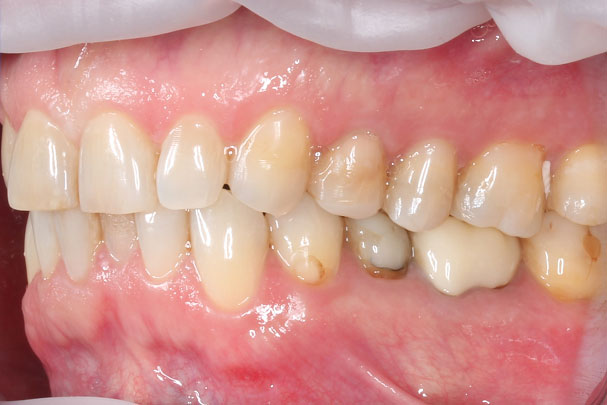

В ходе обследования было обнаружено отсутствие одного зуба и необходимость ортодонтического лечения с целью подготовки к имплантации и протезированию. Стоматолог-ортодонт выявил у пациентки скученность зубов верхней и нижней челюсти и повышенную стираемость зубов (бруксизм). Лечение было назначено на брекет-системе BIOQUICK. Перед ортодонтическими процедурами была проведена санация полости рта. Также на этапе ортодонтии наши врачи установили имплантат и приступили к этапу протезирования.

Было установлено 8 виниров в зоне улыбки: 4 винира на верхние и 4 винира на нижние зубы. Композитом мы восстановили клыковые ведения, установили коронку на имплантат 36 и коронки на зубы 45 и 46.